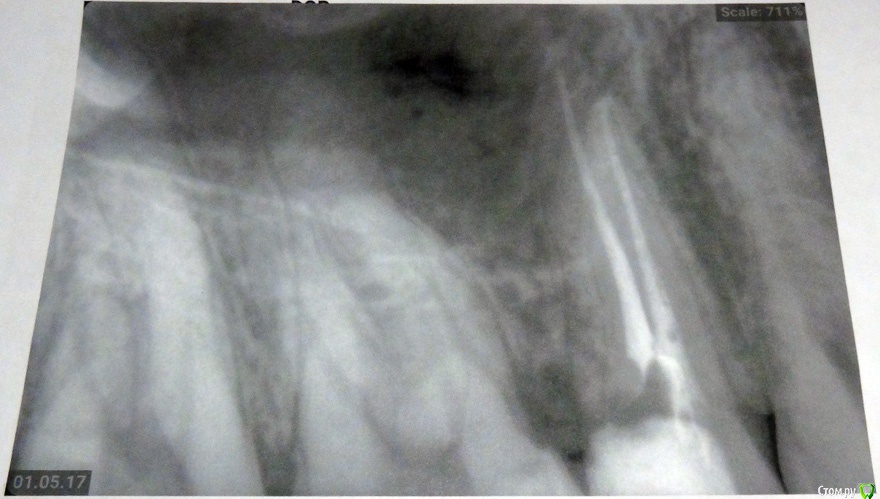

Ниже прилагаю два снимка один - это вроде бы снимок   перед пломбировкой каналов с инструменами.

Второй  -это после пломбировки каналов + временная пломба.

Нормально ли каналы запломбировали?